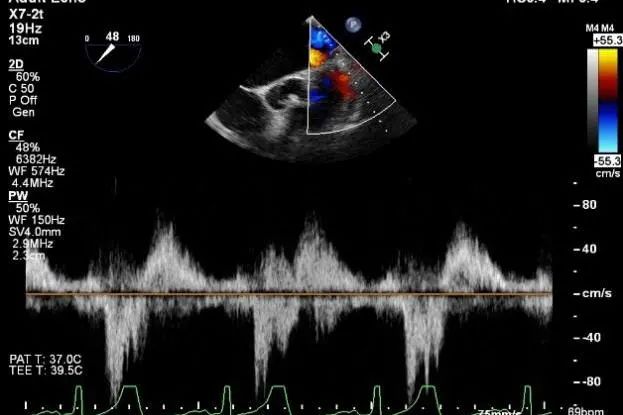

肺静脉收缩期反向血流

术后肺静脉频谱

患者麻醉方式同样采取全麻,建立静脉通路后,穿刺右侧股静脉后,预埋ProGlide缝合器后,送导管至房间隔部位,成功穿刺房间隔后进入左房,调整导管角度,顺利到达二尖瓣目标位置,后在X线及食道超声联合辅助下,宋光远教授使用2枚XTR二尖瓣夹,在精确定位后,准确夹合二尖瓣A2-P2以及A3-P3区域,患者收缩压即刻上升30mmHg,左心房收缩压由62mmHg下降至28mmHg,术中测反流面积明显减少,肺静脉多普勒波形由反向恢复正常。手术顺利结束,术后患者即刻苏醒,安返病房。